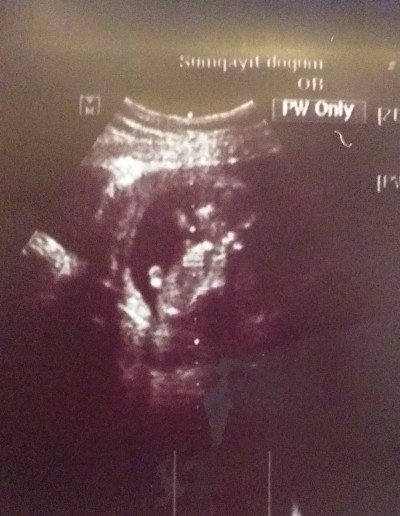

14hafta1gunluken gitmiwdim oglana benziyor dedi yinede net soyluyemem dedi doktor

sizce kizmi ya oglan

Kuzum tam net deil ama erkek doğdu icime